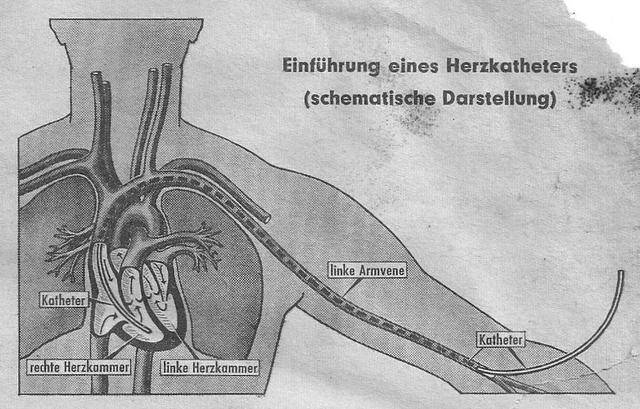

冠狀動脈狹窄

心臟支架手術,簡單來說就通過穿刺血管,讓導管順著血管一路前行。

在導管到達病灶後,再用特殊的傳送裝置將支架輸送到位。

心臟支架手術過程

其實除了打開胸腔,通往心臟的途徑還有一條,那就是全身主要的靜脈。

通過鏡子裡螢光屏的指引,福斯曼再一步一步地將導管深入自己的身體裡。

終於,當導管深入福斯曼體內65釐米時,導管進入了福斯曼的右心房。